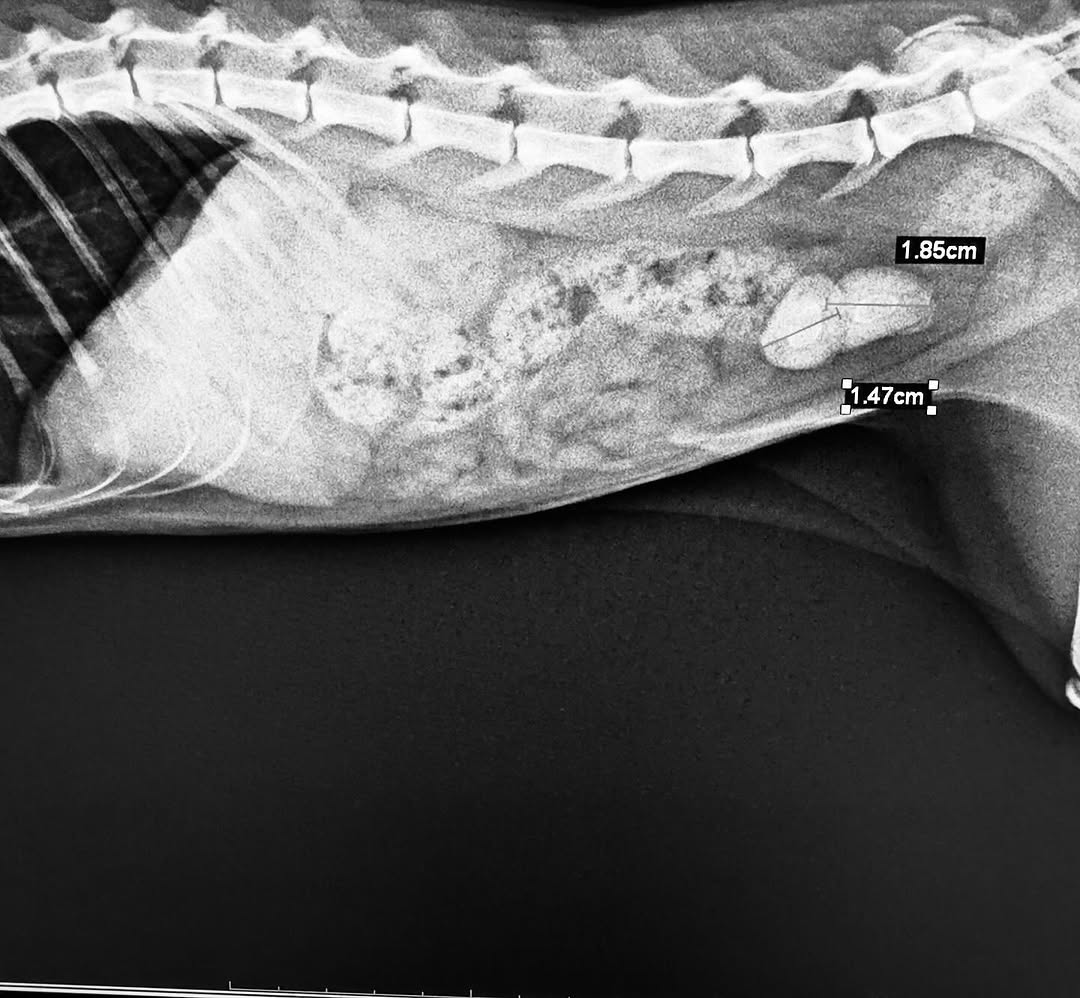

• Röntgen (X-ray): Kemik yapıları, eklem sorunları, kırıklar, iç organların pozisyonları ve göğüs boşluğu hastalıklarının değerlendirilmesinde kullanılır.

• Bilgisayarlı Tomografi (BT/CT): Detaylı kesit görüntüleri sağlayarak tümör, iç kanama, organ hasarları ve bazı beyin hastalıklarının teşhisinde kullanılır.

• Tümör şüphesi bulunan vakalar